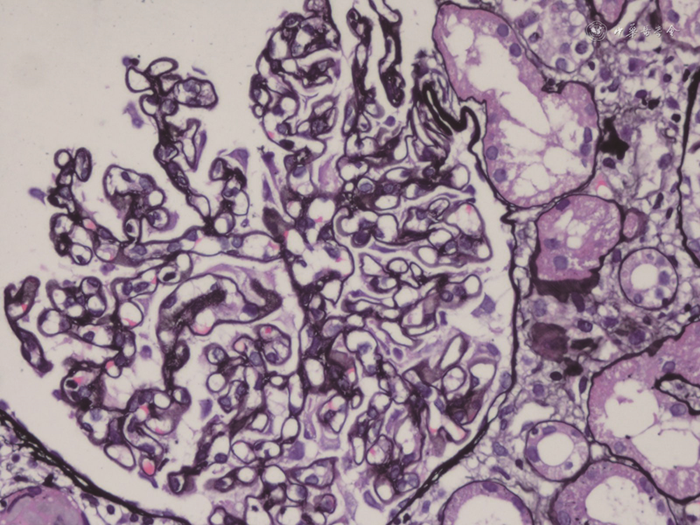

肾活检病理:全片共见约20个肾小球,其中约4个小球球性硬化,个别肾小球稍缺血皱缩,少部分肾小球节段有轻度系膜细胞增生或系膜基质增多,但毛细血管壁明显增厚、僵硬,毛细血管腔开放良好,未见袢坏死或新月体形成,PASM染色见毛细血管壁增厚,部分节段可见钉突和包裹(见图1)。肾小管上皮细胞变性坏死不明显,偶见个别小管萎缩,少数小管中有蛋白管型,间质偶见少量炎细胞浸润,间质纤维化轻微。免疫荧光检查:全片共见约10个肾小球,其中IgA(-),IgM(-),IgG(+),C1q(-),C3(±),Kappa(±),Lambda(±),弥漫性,球性,细颗粒样或线样以毛细血管壁沉积为主。电镜:少部分系膜区可见轻度系膜细胞增生和系膜基质增多,系膜区、内皮下和上皮下电子致密物不明显,内皮细胞胞质内见管网状包涵体,肾小球基底膜(glomerular basement membrane,GBM)明显增厚,基底膜内可见大量微球样膜样结构,足突明显融合(见图2)。肾小管间质未见明显电子致密物。

注:毛细血管壁增厚,部分节段可见钉突和包裹